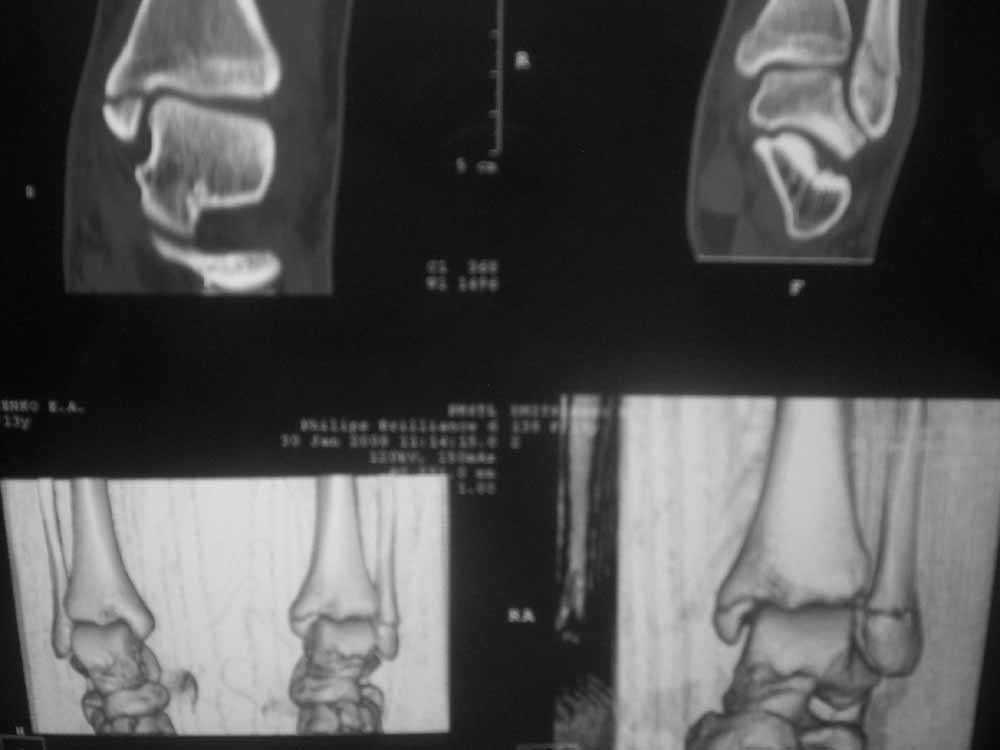

Уважаемые коллеги!Помогите, пожалуйста, советом! Пациентка 14 лет.

Двухлодыжечный

перелом с (как нам кажется) повреждением межберцового синдесмоза.

Вопрос один: оперировать или оставить "как есть" в гипсе? Не будет ли в

дальнейшем проблем с суставом. Заранее спасибо.